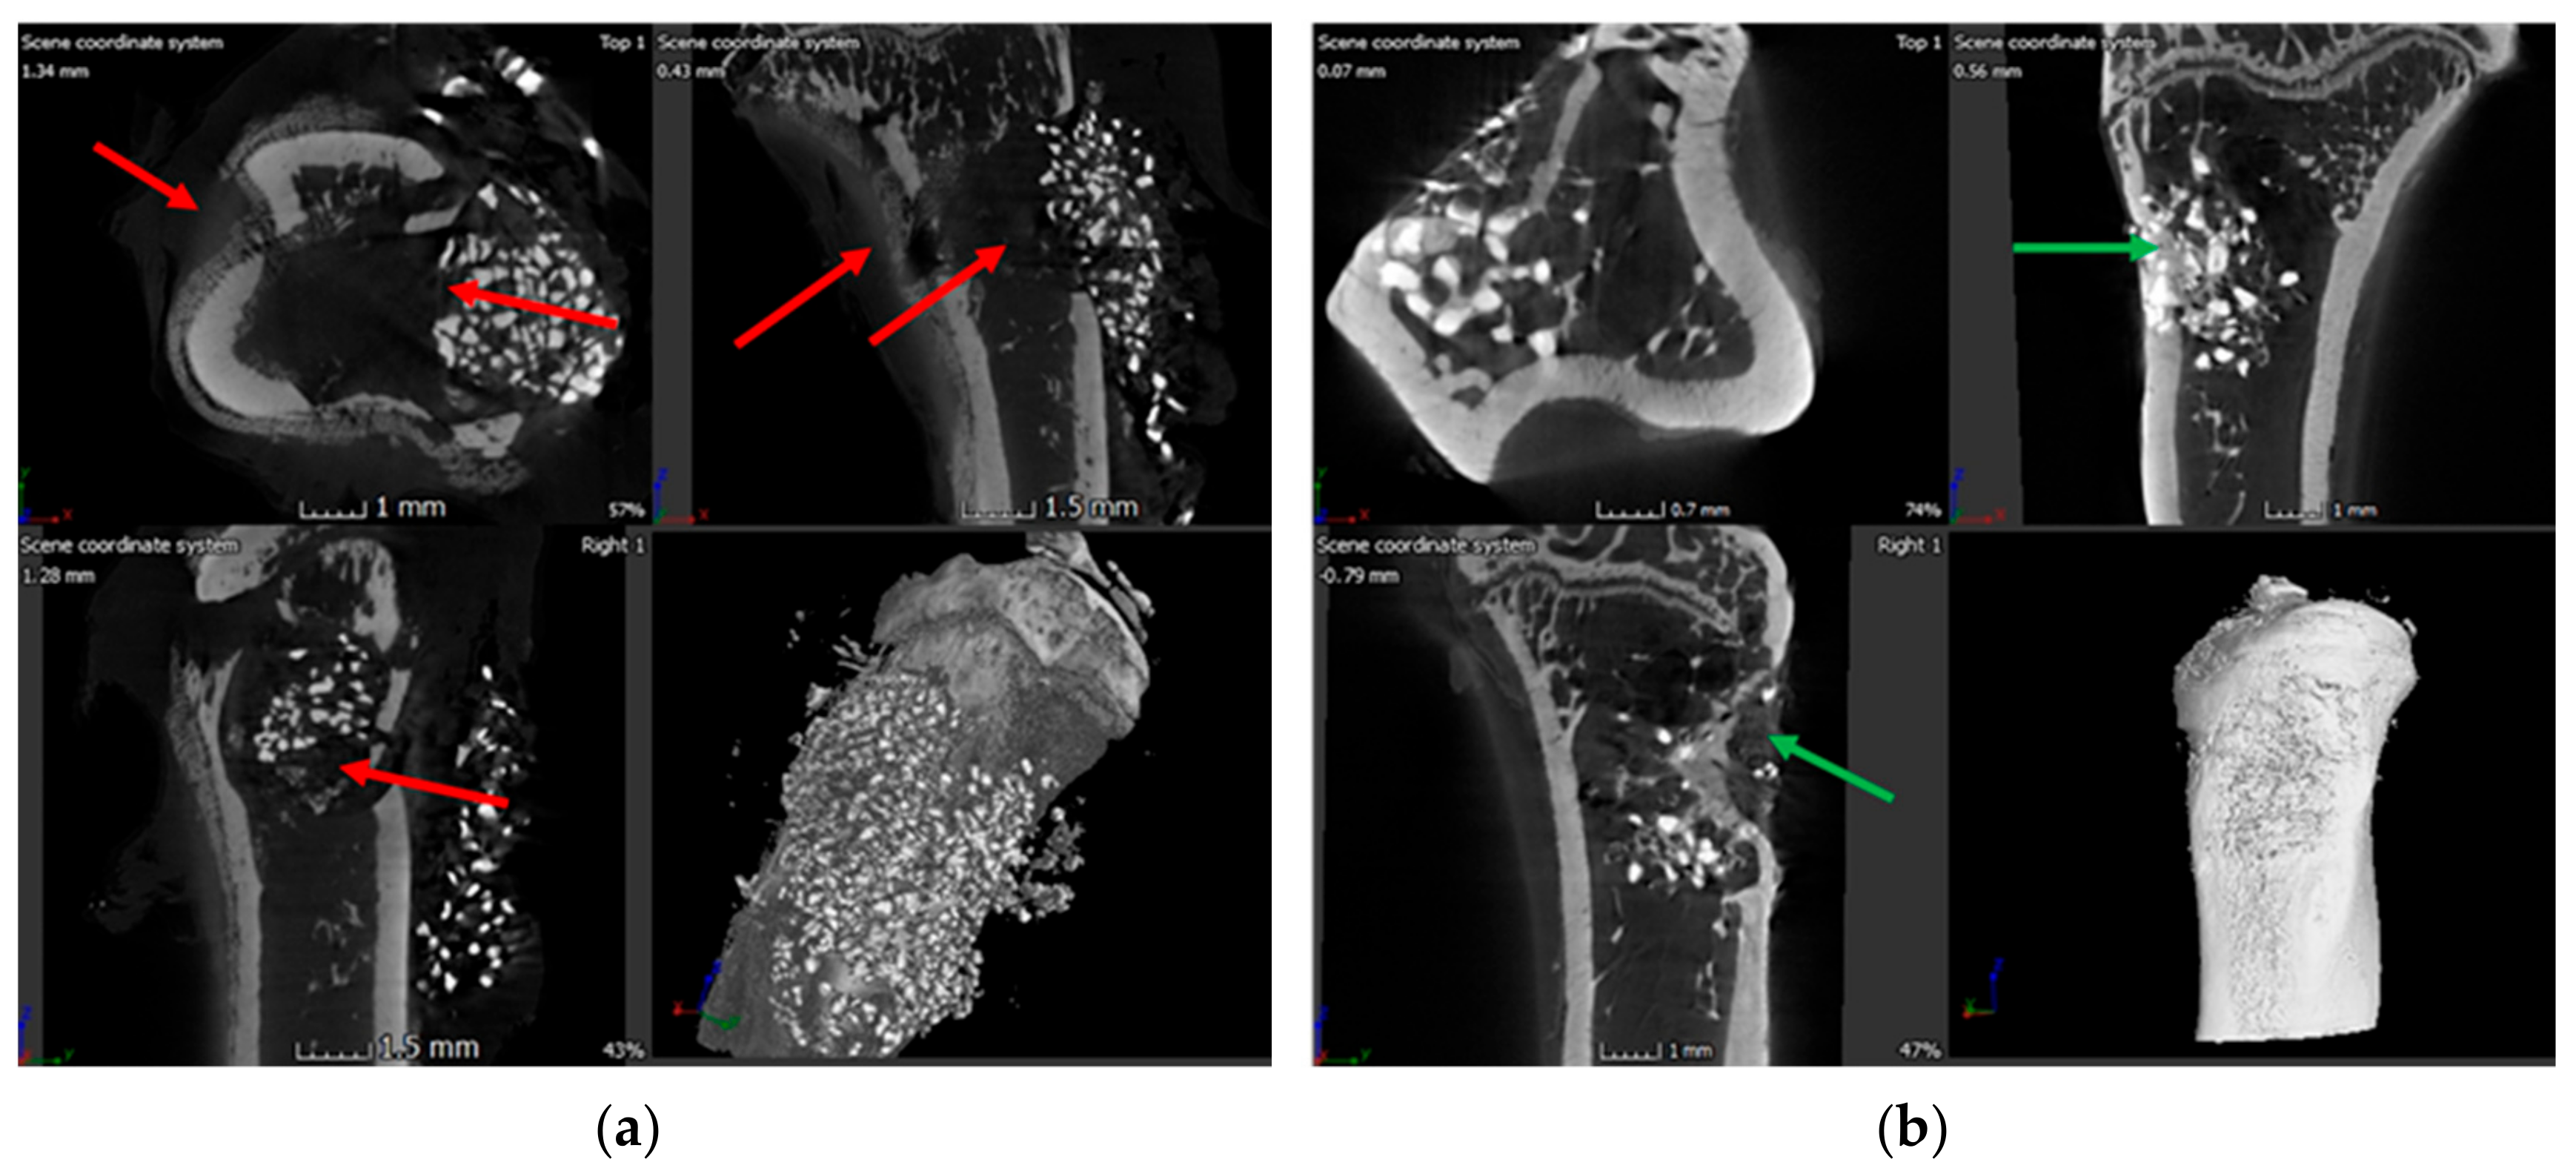

3.6. X-ray and Microcomputed Tomography (μ-CT)

3.7. Bone Volume of Newly Formed Bone